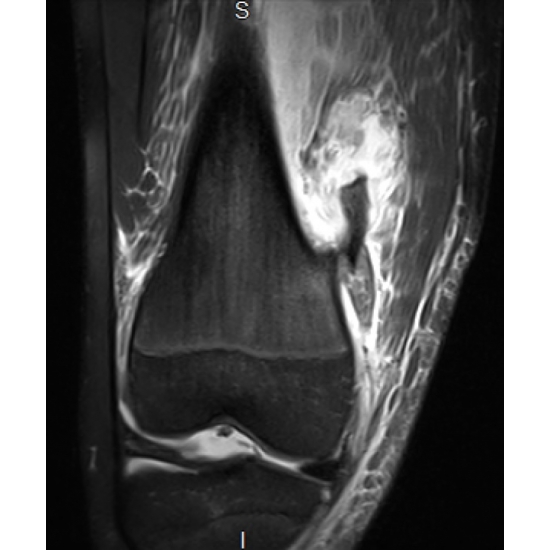

| What Lies Beneath The Bruise - Page #3 | |||